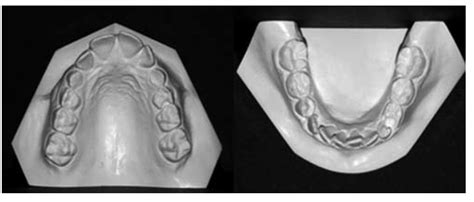

Análisis de Modelos en Máxima Intercuspidación

Modelo superior: Observamos una forma de arcada parabólica, con maxilar comprimido, incisivos superiores diastemados y mesiolinguorrotación de ambos primeros molares superiores (fig. 7A). Modelo inferior: La arcada describe una curva catenaria, con falta de espacio en la región de incisivos inferiores, que se encuentran apiñados. La discrepancia oseodentaria inferior, estimada en función del percentil 75 de las tablas de Moyers, es de -6,6 mm (fig. 7A). Modelos en máxima intercuspidación: Existe una relación molar de Clase II bilateral, siendo completa en el lado derecho e incompleta en el lado izquierdo. La línea media inferior se desvía 1,5 mm hacia la derecha con respecto a la línea media superior. El resalte está aumentado, siendo de +11 mm. Podemos calificar la sobremordida como completa o de 3/3 (fig. 7B).

Figura 7A. Vista oclusal de modelos pretratamiento.

Figura 7B. Modelos pretratamiento en máxima intercuspidación.